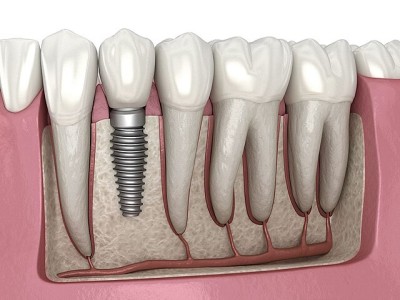

Single Tooth Implant

Replaces one missing tooth in a fixed and secure way.